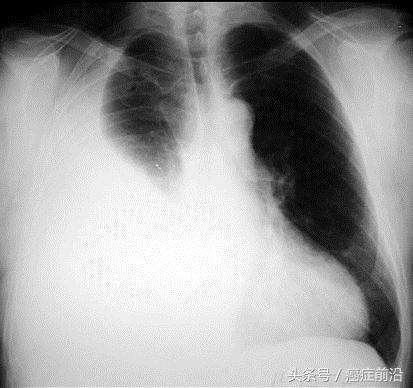

胸部X线检查可以明确胸腔积液量。CT可以了解大致胸腔积液量和胸腔积液引流后的占位病变。B超检查可了解胸腔积液量并对胸腔穿刺有定位作用。

胸腔积液影像检查图片